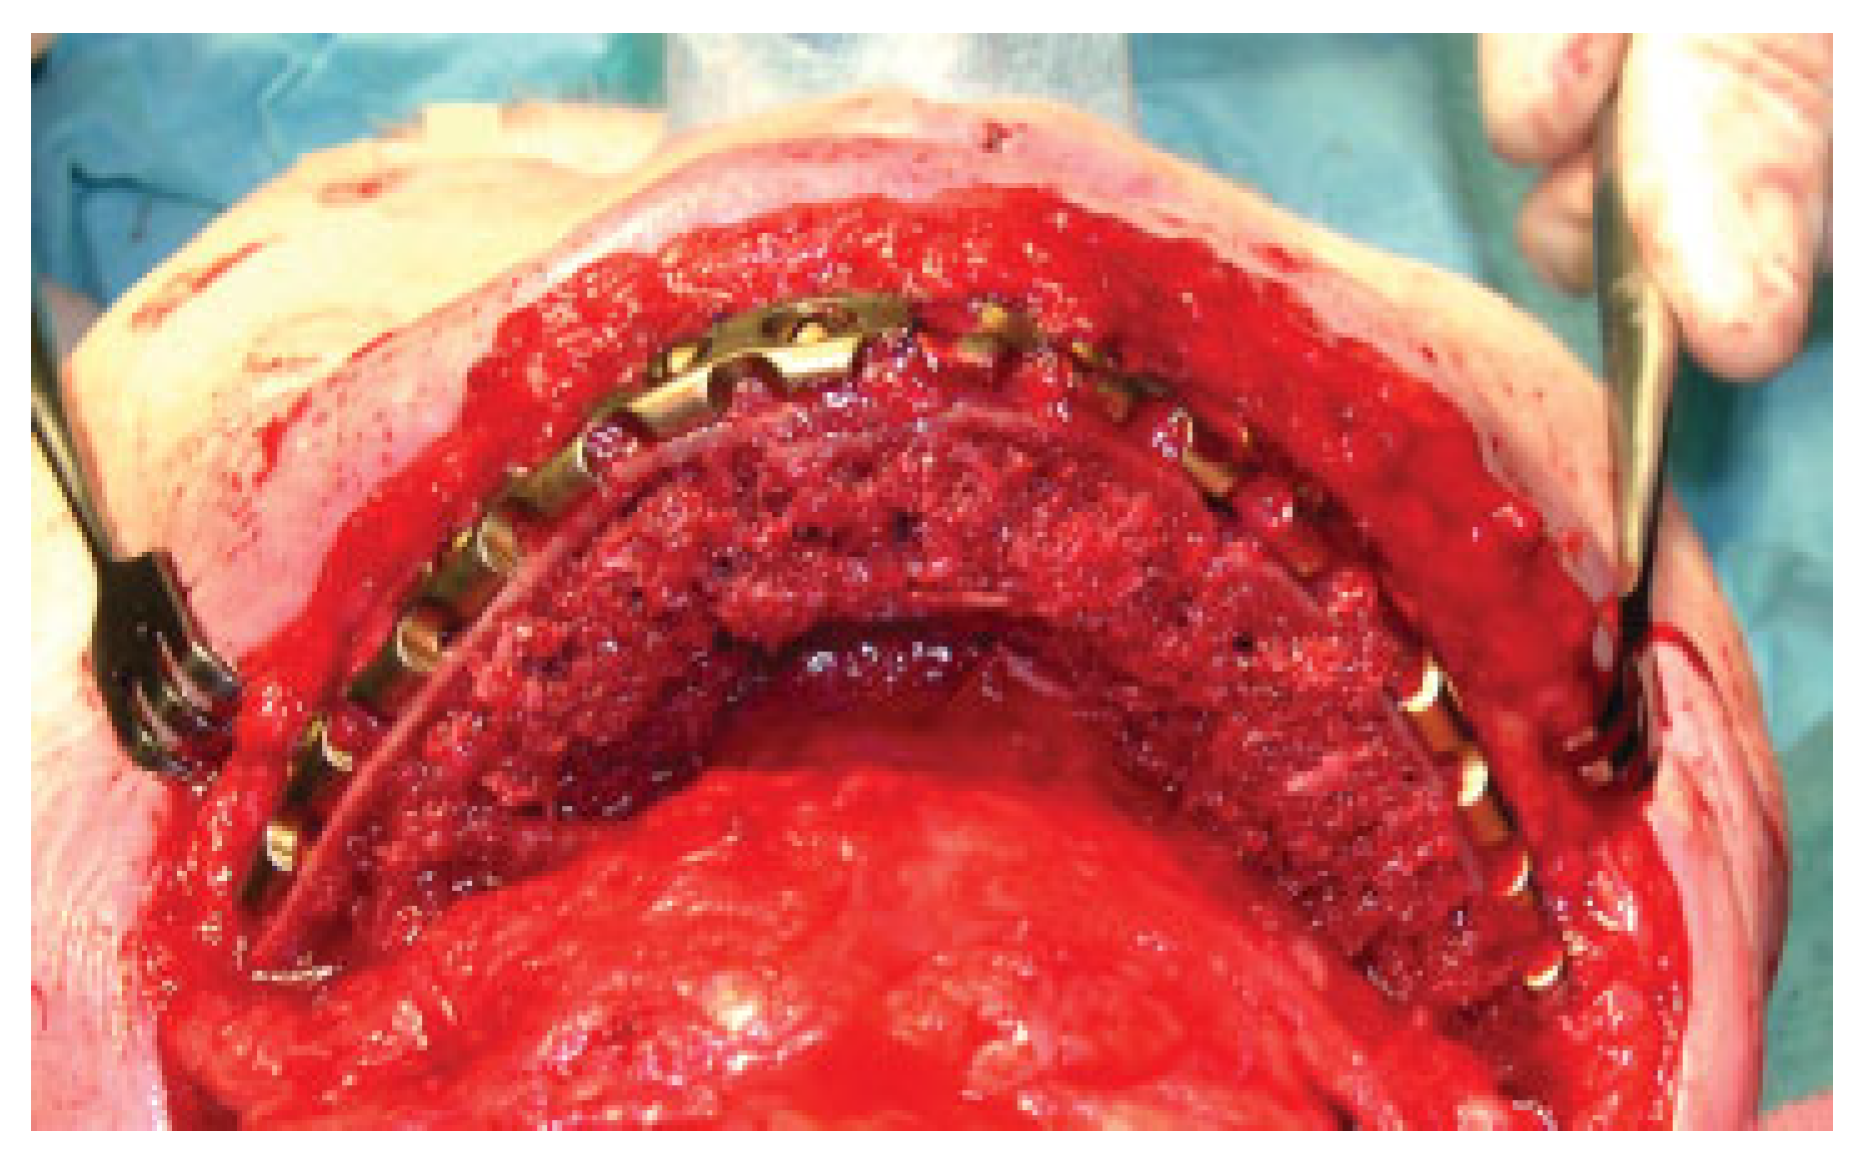

A submandibular incision is made well beneath the body and angle of the mandible to expose the site to be reconstructed, avoiding the mandibular branch of the facial nerve. Supplementary resection is performed if needed. In dentate patients, the teeth are brought in occlusion and the mandible is immobilized through maxillomandibular fixation. A reconstruction plate is then fixed onto the mandible, preferably with three screws placed on either side of the resection stumps according to recognized AO principles [13] (Figure 2). The flap is inserted as a muscle fan with the skin island covering the external defect and the internal aspect sutured under the mucosal defect if present. The muscle fan is wrapped around the plate and the mandibular stumps, and sutured in place (Figure 3). The oral soft tissue wound will shrink and epithelize quickly obviating the need for a skin graft.

Figure 3. Reentry with latissimus dorsi flap wrapped around reconstruction plate and resection stumps before closure with skin pad.